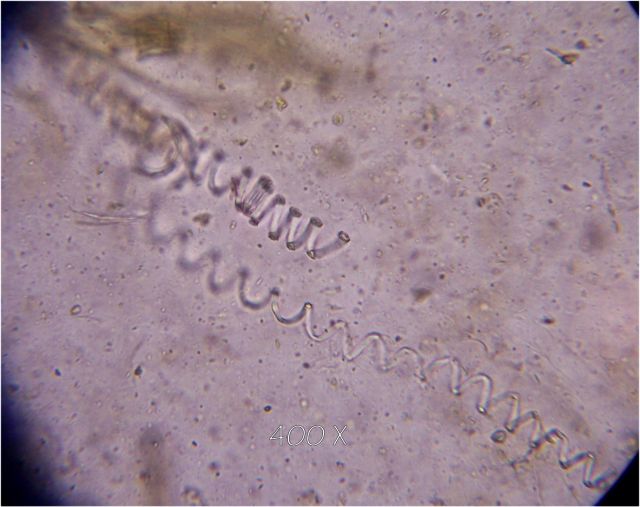

Fecal Exams

images/worm.jpg

images/Nema.jpg